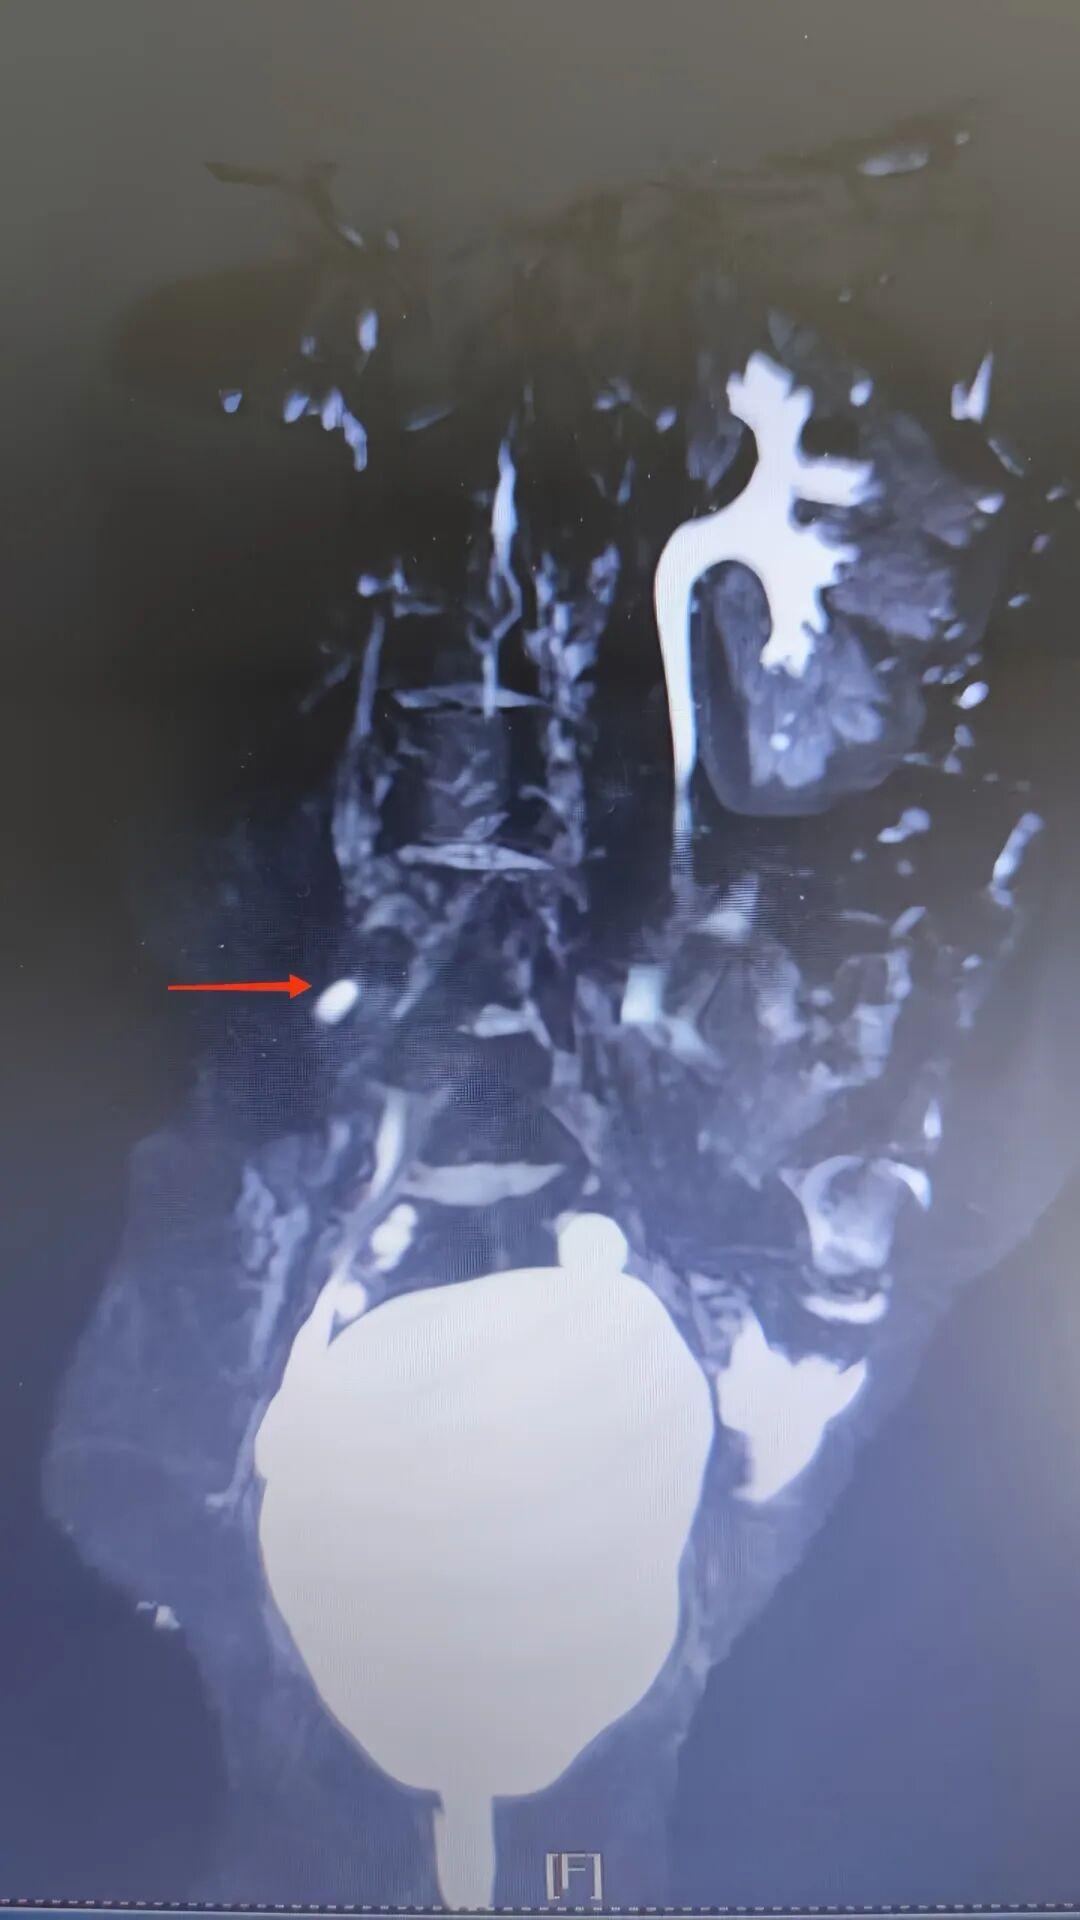

接诊后,小儿泌尿外科主任高强凭借丰富的临床经验,并未将小玉的症状简单归为排尿控制能力差。结合患儿长期漏尿的病史,医生为小玉完善了超声、MRI 尿路成像(MRU)、CT 等一系列检查,最终明确诊断为右肾发育不良伴输尿管异位开口。

在泌尿系统中,输尿管起着将肾脏产生的尿液输送至膀胱的关键作用。正常情况下,输尿管开口于膀胱三角区,确保尿液有序储存与排出。输尿管异位开口,顾名思义,就是输尿管未按正常生理结构开口于膀胱三角区,而是“跑偏”到了其他部位——如前庭、阴道、尿道等处,尿液便不受膀胱控制,直接从这些异位开口流出,进而导致持续性尿失禁。这种尿失禁不仅严重影响患者的生活质量,还可能引发外阴部湿疹、皮肤糜烂等一系列并发症。